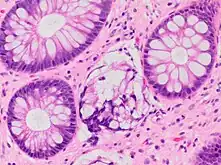

| A micrograph demonstrating cryptitis, a microscopic correlate of colitis. H&E stain. | |

An important investigation in the assessment of colitis is biopsy for histopathology. A very small piece of tissue (usually about 2mm) is removed from the bowel mucosa during endoscopy and examined under the microscope by a histopathologist. A biopsy report generally does not state the diagnosis, but should state any presence of chronic colitis, give an indication of disease activity, as well as state the presence of any epithelial damage (erosions and ulcerations).[4]

Histopathology findings generally associated with chronic colitis include:[4]

Crypt degeneration

Crypt branching and other architectural distortions

Paneth cell (pictured) or gastric metaplasia (only applies in the left colon and rectum)

Other findings include basal plasmacytosis and mucin depletion.[4] Histopathology findings generally associated with active colitis include:[4]

Neutrophilic cryptitis (neutrophils within crypt epithelium)

Crypt abscesses (luminal neutrophilic aggregates)

Gland destruction

Ulceration (seen here as absence of epithelium, and granulation tissue with many fibroblasts)